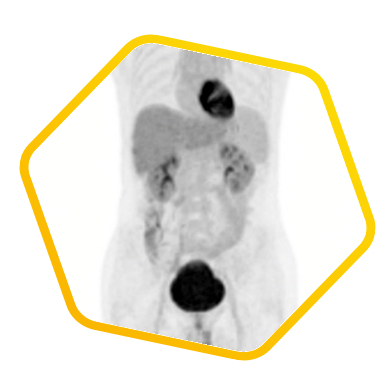

Myeloma

![]() [C-11] Acetate |

![]() [F-18] FDG |